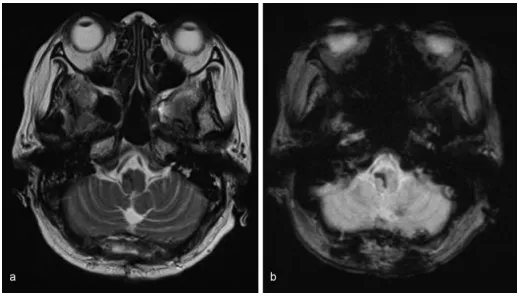

术中神经生理监测(运动诱发电位和感觉诱发电位)保持不变。术中无海绵状畸形等病理学证据。术后CT显示血肿消失。

图:术后电脑断层扫描显示延髓血肿消失

手术后,她的自主唿吸提高到每分钟15次以上。术后第5天停止唿吸机支持,术后第6天拔管。术后5周核磁共振成像显示无结构异常。康复后,自主步行出院,没有进一步的并发症。

图:术后5周磁共振成像未见结构异常。